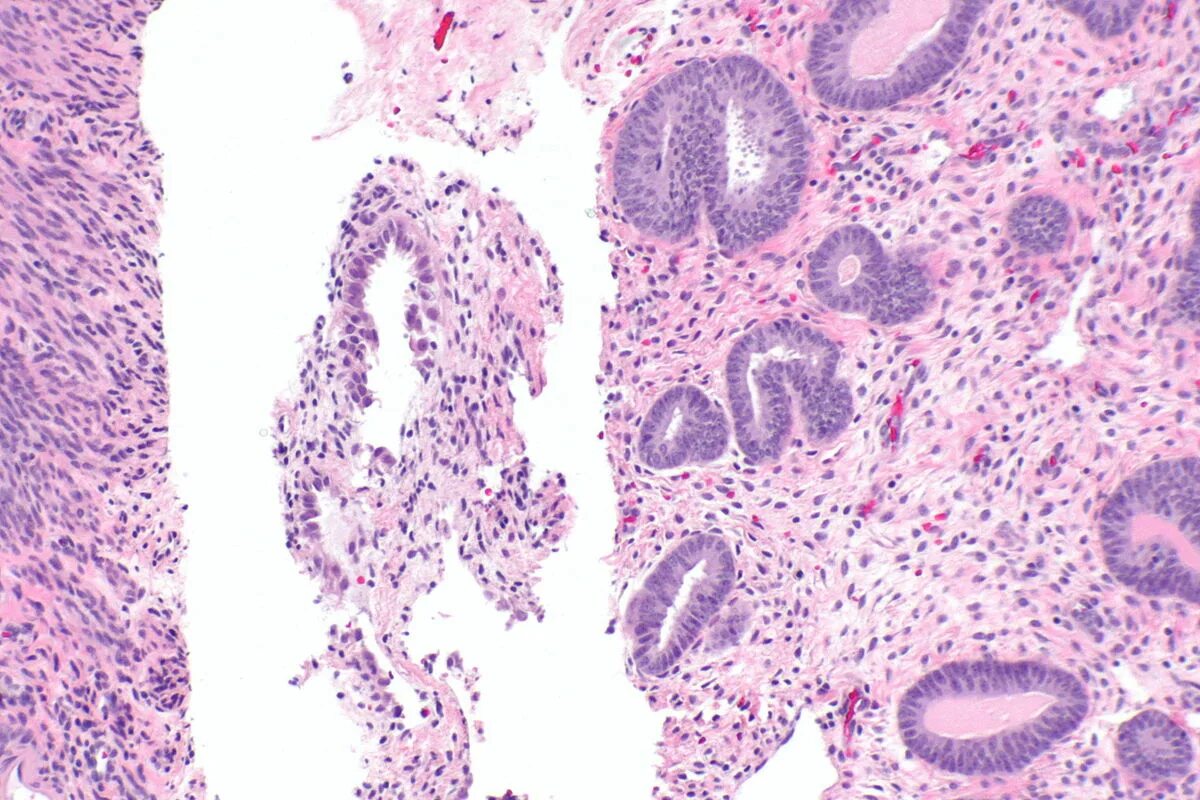

Гистологическое исследование полипов